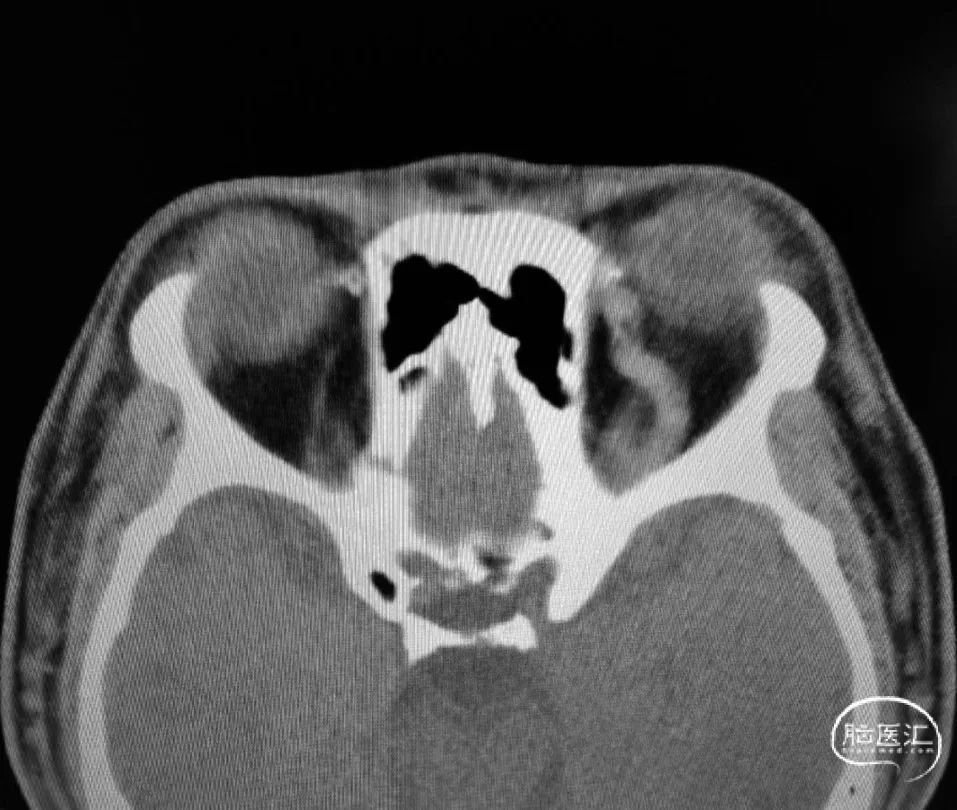

术前CT见左侧眼上静脉扩张

术后铸胶形态及CT下铸胶位置,可见瘘口位于左侧舌下神经管区域。